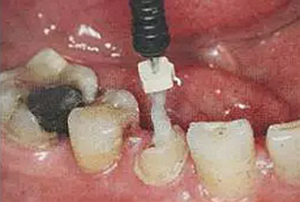

(超聲去除根管殘留物)

通常此時(shí)以超聲潔牙機(jī)更換較細(xì)工作尖進(jìn)入根管(根管消毒沖洗液配合清潔工作后面會(huì)提到),徹底去除樁道根管壁上的附著殘留物,效果明顯。再配合X線片、根管顯微鏡輔助檢查清理的情況下更佳。